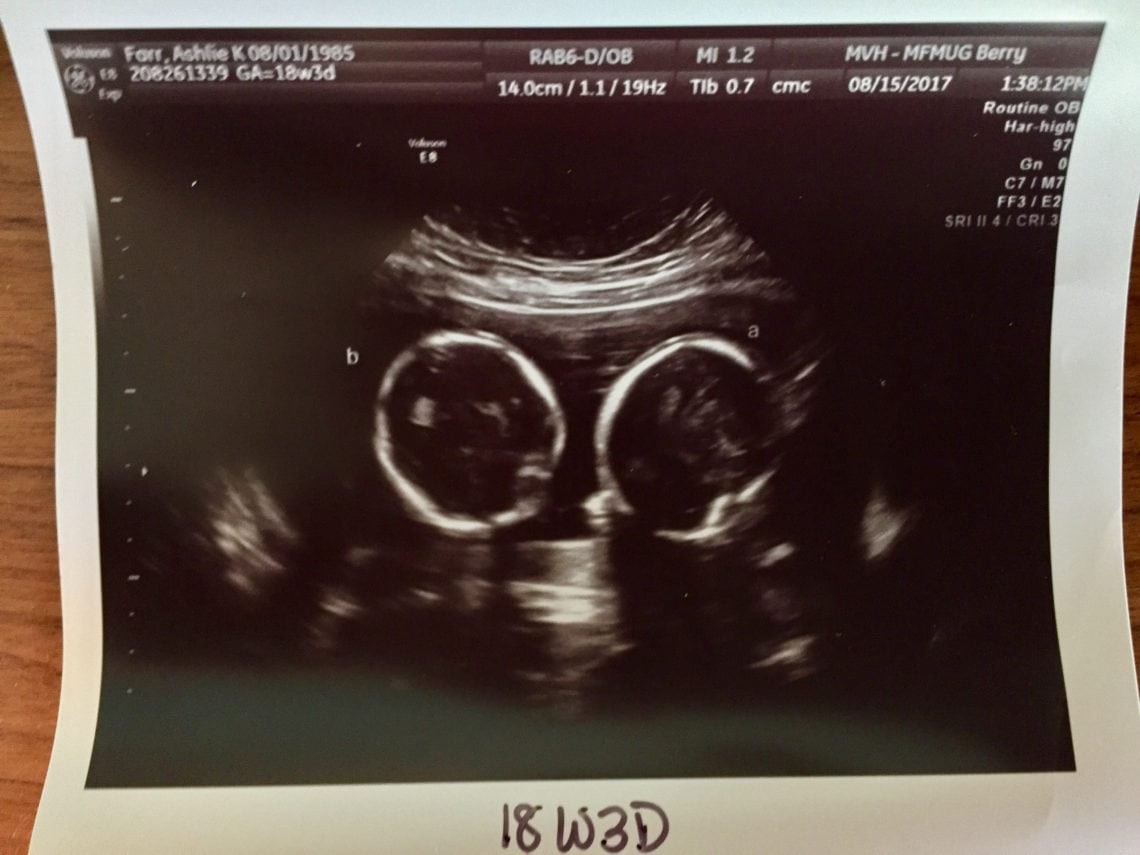

Did You Find Out It Was Twins At Later Ultrasound? Twin Ultrasound

Did You Find Out It Was Twins At Later Ultrasound? Twin Ultrasound How Often Are Twins Missed On Early Ultrasound When do twins show up on ultrasound? In some cases, healthcare providers may be able to identify the presence of twins even earlier, especially with advanced ultrasound technology. Learn about the causes, signs and risks of hidden twins, and how ultrasounds can help detect them. Transvaginal ultrasounds can detect twins as early as 5 to 6 weeks gestation, while abdominal. How Often Are Twins Missed On Early Ultrasound.

Did You Find Out It Was Twins At Later Ultrasound? Twin Ultrasound How Often Are Twins Missed On Early Ultrasound Twins can typically be detected on ultrasound during the first trimester, usually around 6 to 8 weeks of gestation. As twins continue to increase in frequency, 4 routine ultrasound surveillance for. Transvaginal ultrasounds can detect twins as early as 5 to 6 weeks gestation, while abdominal ultrasounds can usually detect twins between 6 to 8 weeks. The ability to visualize. How Often Are Twins Missed On Early Ultrasound.

Did You Find Out It Was Twins At A Later Ultrasound? Twiniversity 1 How Often Are Twins Missed On Early Ultrasound In some cases, healthcare providers may be able to identify the presence of twins even earlier, especially with advanced ultrasound technology. Ultrasound tech was surprised she missed it at my 8 week ultrasound. Transvaginal ultrasounds can detect twins as early as 5 to 6 weeks gestation, while abdominal ultrasounds can usually detect twins between 6 to 8 weeks. I had. How Often Are Twins Missed On Early Ultrasound.

Did You Find Out It Was Twins At A Later Ultrasound? Twiniversity 1 How Often Are Twins Missed On Early Ultrasound Twins can typically be detected on ultrasound during the first trimester, usually around 6 to 8 weeks of gestation. Twins can be missed in early pregnancy, but it's rare and unlikely after 10 weeks. Twins can often be detected early in pregnancy through ultrasound imaging. The ability to visualize twins on an. Ultrasound tech was surprised she missed it at. How Often Are Twins Missed On Early Ultrasound.

Did You Find Out It Was Twins At A Later Ultrasound? Twiniversity 1 How Often Are Twins Missed On Early Ultrasound Learn about the causes, signs and risks of hidden twins, and how ultrasounds can help detect them. How often are twins missed on the first ultrasound? Twins can often be detected early in pregnancy through ultrasound imaging. Twins can be missed in early pregnancy, but it's rare and unlikely after 10 weeks. I had an ultrasound today 12w2d showing 2. How Often Are Twins Missed On Early Ultrasound.

Did You Find Out It Was Twins At Later Ultrasound? Twin Ultrasound How Often Are Twins Missed On Early Ultrasound Twins can typically be detected on ultrasound during the first trimester, usually around 6 to 8 weeks of gestation. Transvaginal ultrasounds can detect twins as early as 5 to 6 weeks gestation, while abdominal ultrasounds can usually detect twins between 6 to 8 weeks. Ultrasound tech was surprised she missed it at my 8 week ultrasound. How often are twins. How Often Are Twins Missed On Early Ultrasound.